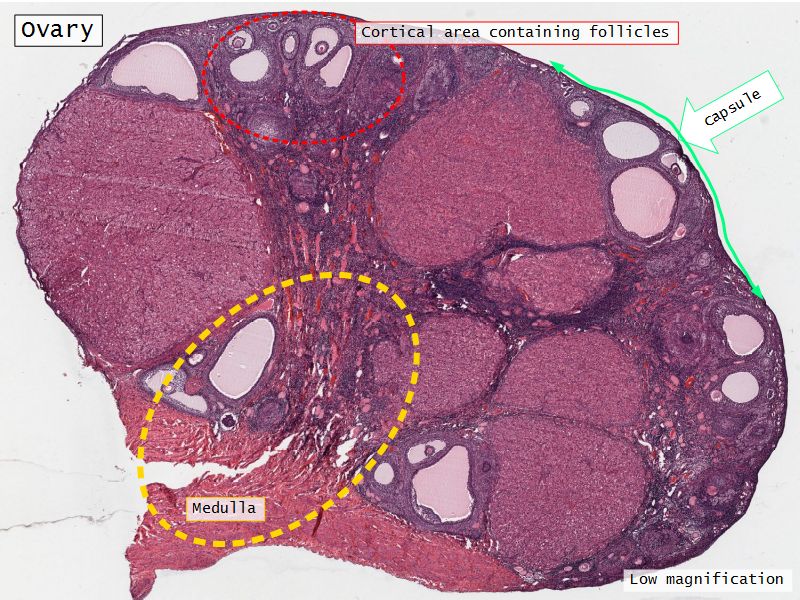

Ovary

- Capsule covered by modification of peritoneum

- Called germinal epithelium

- Simple squamous/cuboidal

- Subdivided

- Not clearly defined

- Cortex - contains ovarian follicles

- Medulla - vascular

Cortex

- Tunica albuginea

- Irregular dense CT capsule

- Follicles in various phases

- Stroma containing follicles

Medulla

- Blood vessels

- Hilus cells

- Stroma